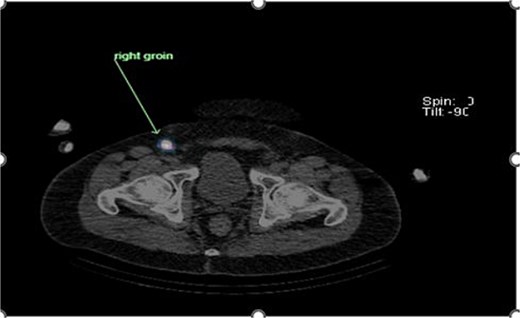

Preoperative lymphoscintigraphy was performed to detect the sentinel lymph node (Fig. 1), expecting it to be in the right inguinal region (Fig. 2). However, drainage to both the right axillary (Fig. 3) and inguinal areas was demonstrated. During surgery, a gamma camera confirmed drainage to both regions (Fig. 4). Blue dye was injected around the previous scar, and sentinel nodes were dissected guided by both blue dye and gamma camera for histopathology.

Lymphoscintigraphy showing drainage from the right lower back lesion.